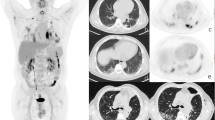

In terms of SUV parameters, there were no significant differences between patients with and without postoperative complications (Table 1, Fig. 2A). However, all SUV parameters, except the SUVmean, in patients with postoperative AE were significantly higher than those in patients without postoperative AE (Fig. 2B, Additional file 1: Table S2). The SUV parameters were not significantly different between patients with and without prolonged air leakage (Fig. 2C) and between survivors and non-survivors (Fig. 2D).

Comparison of baseline SUVs between IPF patients with and without postoperative complications. A All complications. B Acute exacerbation. C Prolonged air leakage. D Death. Each bar represents the mean and standard deviation. *p< 0.05, #p < 0.1. SUV, maximum standardized uptake value; IPF, idiopathic pulmonary fibrosis; Cx, complications; SUVmax, maximum standardized uptake value; SUVmean, mean standardized uptake value; SUVR, standardized uptake value ratio; SUVmeanTF, tissue fraction-corrected mean standardized uptake; SUVRTF, tissue fraction-corrected standardized uptake value ratio; AE, acute exacerbation; AL, air leakage